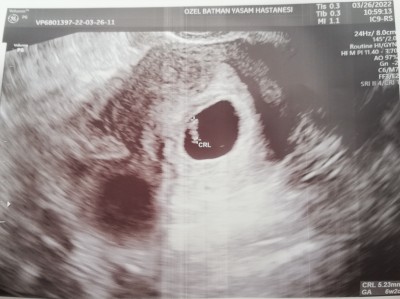

Son adet göre 7 haftalık ultrasonda 6+2 hamileyim. Kalp atışı yok. Bebeğin boyutu 5. 23 mm görünüyor normalde kalbi atması gerekmez miydi. Alttan baktı duyamadı. Çok üzgünüm çok korkuyorum bir düşük daha olmasın duanızı istiyorum. Ağlamak istiyorum ağlayamıyorum sadece korkuyorum ☹️ Geç duyanlar bebeğin boyutu kaçtı ultrasonda. Normalde alttan duyulmalıydi o olmadı salı günü başka doktora gidecem ☹️

7+6 da duyuldu oğlumun

Evet evet mesela son adetime göre 8+3 tü am ultrasonda 7+6

8+5 ken hep 6+4 görünüyodu 4-5 defa gittim kalp atisi icin gec duyduk

Ultrasonda bebek ölçümünuz kaç haftalikken duydunuz kalbini. İşte son adet tarihim göre olmadı 7 görünüyordu ama ultrasonda 6+2 görünüyor